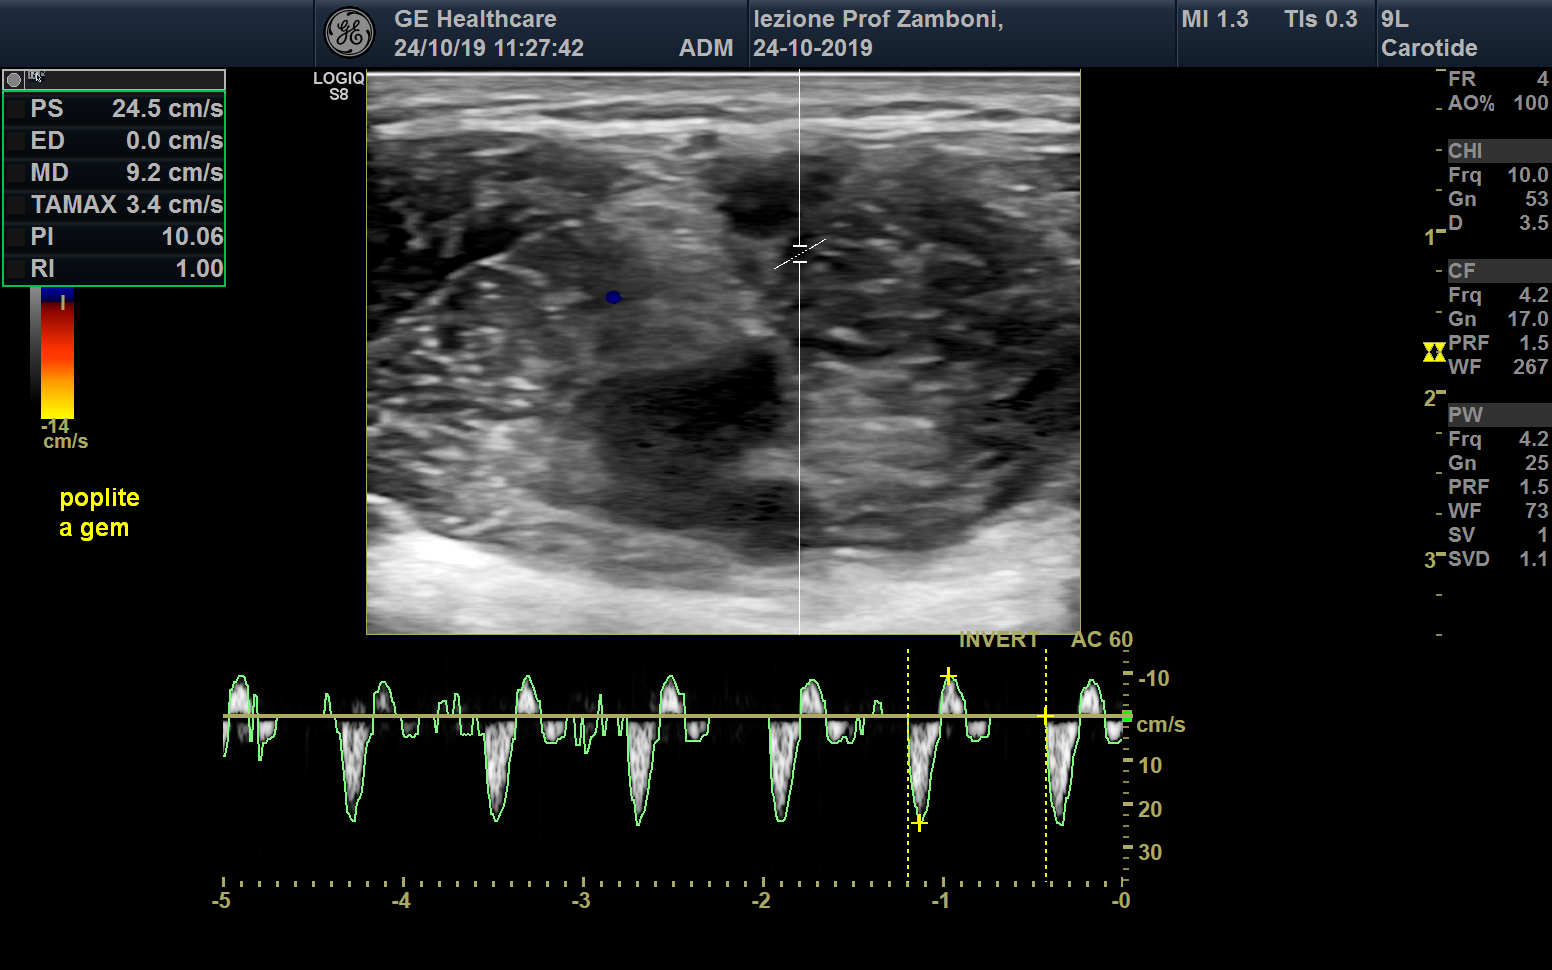

PW A. gemellare

JPEG image icon PW A. gemellare.jpg — JPEG image, 616 kB (631366 bytes)